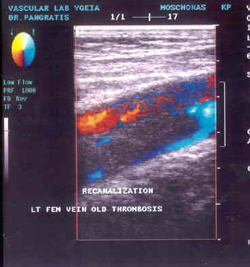

ΧΡΟΝΙΑ

ΘΡΟΜΒΩΣΗ

Με την πάροδο του χρόνου ο θρόμβος γίνεται σκληρότερος και οργανώνεται, πορεία

που συμβαδίζει με τα υπερηχογραφικά χαρακτηριστικά, αφού ο πρόσφατος θρόμβος

είναι σπογγώδης και ευμετάβλητος και καθώς παρέρχεται ο χρόνος, εξωτερική ελαφρά

ή μέτρια πίεση της φλέβας δεν συμπιέζει το θρόμβο. Σε παλαιούς θρόμβους, τα

τοιχώματα της φλέβας δεν εφάπτονται, ακόμη και εάν εφαρμοσθεί πίεση που προκαλεί

απόφραξη παρακείμενης αρτηρίας. Ένα άλλο χαρακτηριστικό επίσης είναι η αυξημένη

ηχογένεια του παλαιού θρόμβου, έτσι ώστε "όσο παλαιότερος ο θρόμβος είναι,

τόσο μεγαλύτερη ηχογένεια έχει", ενώ με την πάροδο αρκετού χρονικού διαστήματος,

ο θρόμβος έχει τέτοια υπερηχογραφική εμφάνιση, ώστε είναι δύσκολο να εξακριβωθεί

και να διευκρινισθεί από τους γύρω ιστούς. Δεν είναι σπάνιο γεγονός εξετασθείς

ασθενής με θρόμβωση προ πολλών ετών και να μην παρατηρείται φλεβικό στέλεχος

στην αναμενόμενη θέση παρά την αρτηρία. Επίσης, δεν αποφράσσουν τη φλέβα όλοι

οι παλαιοί θρόμβοι, αλλά απλώς προσκολλώνται στο τοίχωμα (επανασηρραγγοίηση).

Σε κάθε περίπτωση υπάρχει ανώμαλος υπολειμματικός θρόμβος, που θυμίζει αρτηριακή

αθηρωματική πλάκα κατά μήκος μίας ή και των δύο επιφανειών.